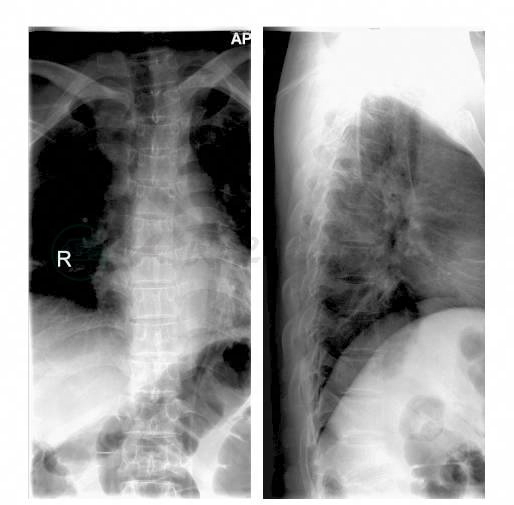

胸椎正侧位X线片示T12椎体压缩骨折,前缘压缩近50%,中后结构尚完整(图1)。

图1 胸椎正侧位X线片示T12椎体压缩性骨折,前缘压缩近50%